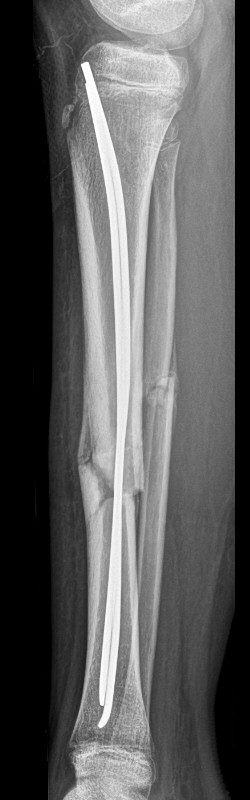

Tibia och fibula-frakturer, tibia spikats med 2 TEN-spik, sista 2 bilderna efter 5 veckor, då inte alls ömmande över frakturerna.